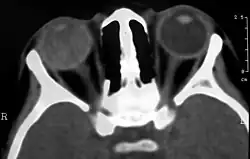

On CT, the globe appears hyperdense compared to normal vitreous due to the proteinaceous exudate, which may obliterate the vitreous space in advanced disease. The anterior margin of the subretinal exudate enhances with contrast. Since the retina is fixed posteriorly at the optic disc, this enhancement has a V-shaped configuration.[2]